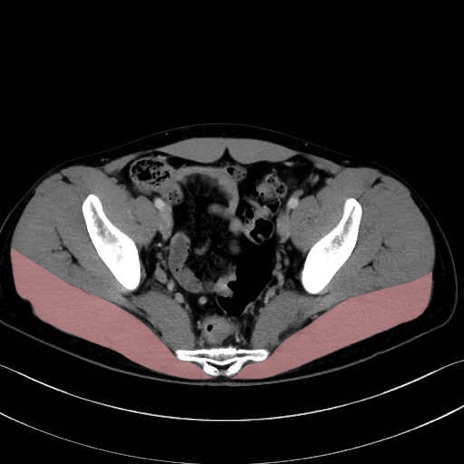

大殿筋 (Gluteus maximus)